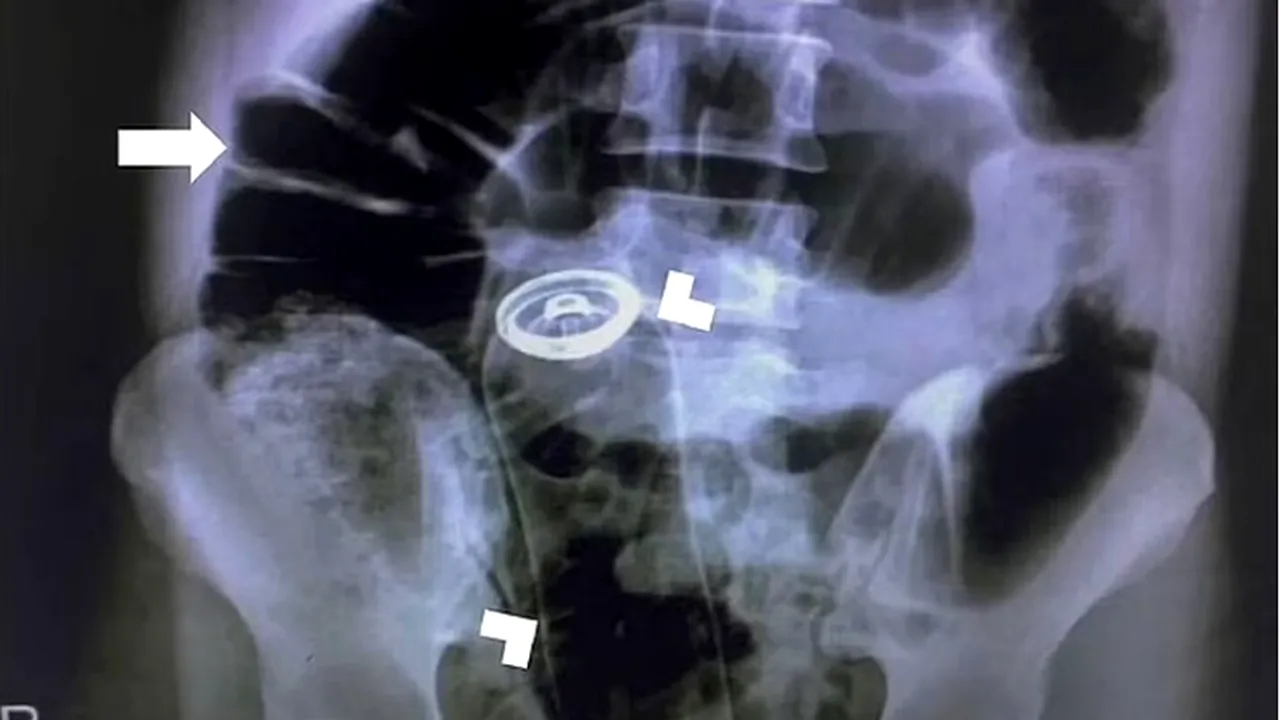

Un bărbat s-a prezentat la urgențe cu un deodorant în abdomen pe care și l-a introdus prin anus / Sursa foto: Daily Mail

Medicii au fost nevoiți să opereze de urgență un bărbat de 30 de ani care s-a prezentat la spital cu un deodorant blocat în anus. Cadrele medicale nu au avut altă variantă de a-i înlătura obiectul decât printr-o operație la nivelul stomacului.

Bărbatul de 30 de ani s-a prezentat la urgențe, după ce și-a introdus un deodorant în fund, iar acesta i s-a blocat în anus. Inițial, pacientul nu a vrut să vină la spital, dar, după două ore de dureri îngrozitoare, a ales să se adreseze cadrelor medicale.

În fața acestui caz complicat, medicii trebuiau să găsească o soluție de extragere a tubului de deodorant, fără a-i deteriora anusul.

Chirurgii nu au vrut să riște, așa că i-au tăiat stomacul bărbatului, scoțându-i astfel recipientul din anus, relatează Daily Star.

După operație, care a avut loc în aripa de urgență cadrul Universității de Științe Medicale din Teheran, pacientul a mai rămas o zi în spital, pentru a fi ținut sub observație și pentru a se recupera după intervenție.